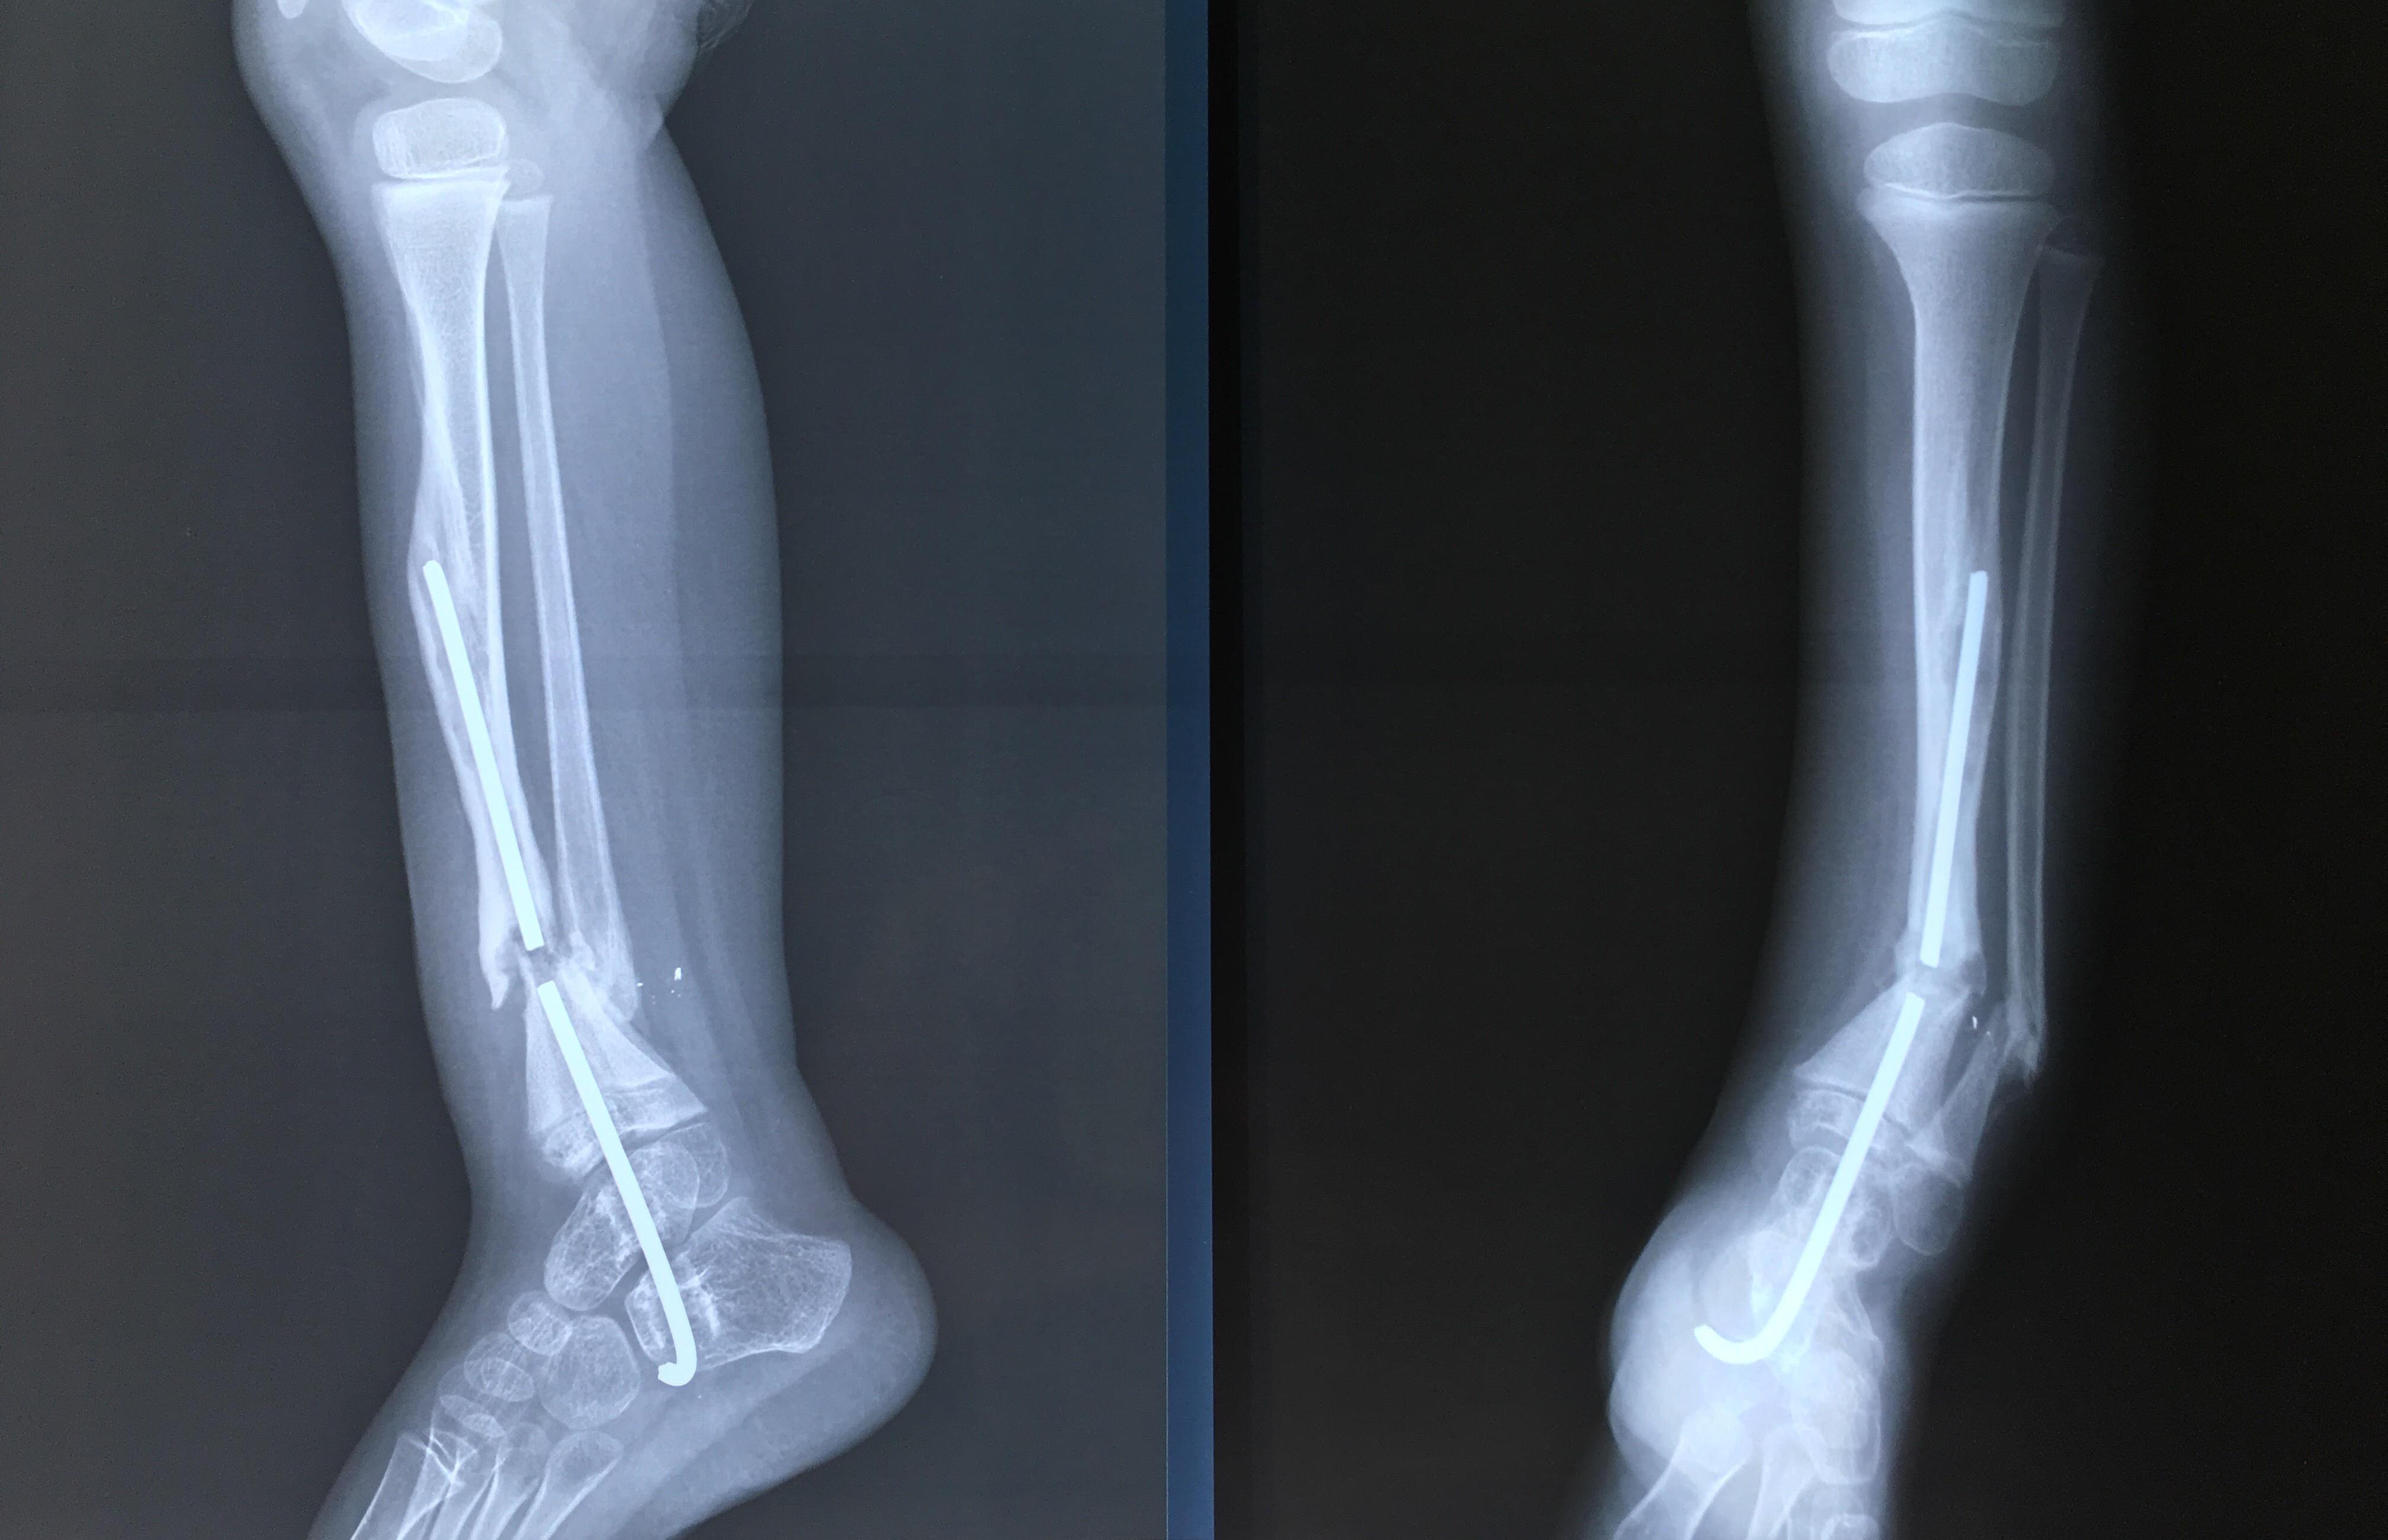

Phẫu thuật thành công ca bệnh hiếm gặp...khớp giả bẩm sinh xương chày

26/06/2019 17:00

Đã xem: 3515

Bệnh viện Chấn thương- Chỉnh hình Nghệ An, vừa phẫu thuật thành công cho bệnh nhi khớp giả bẩm sinh xương chày